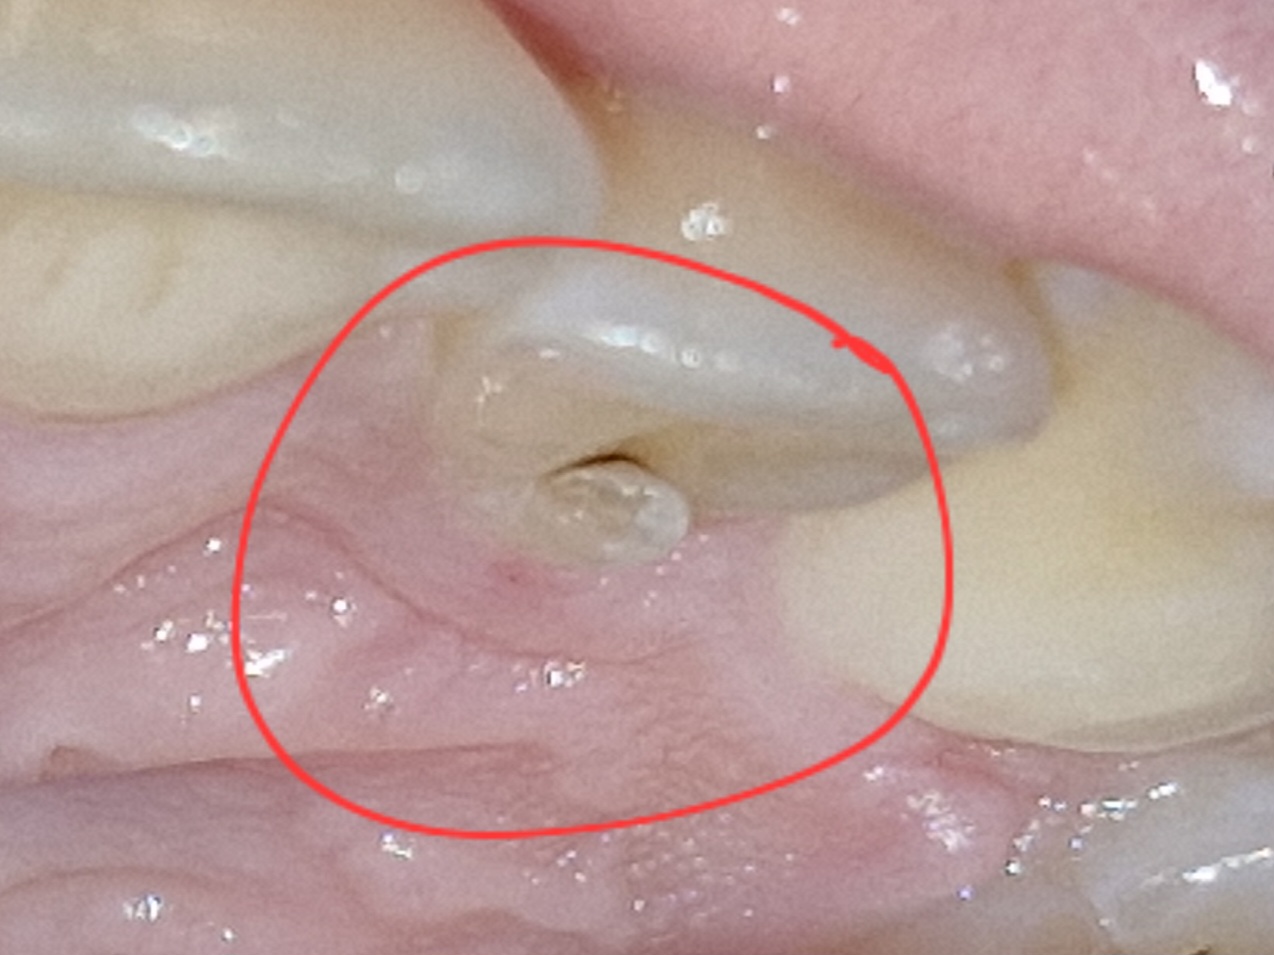

@euka210 a nevadí ze to je až úplne dolu? To vyzerá už jak pod dasnom...ja som strašná v tomto, posrata som :D

Ťažko povedať, lebo ak je to hlboké tak to zlomené vyberie a podľa toho buď dorobí alebo rovno vytrhne....nie vždy sa dá zlomený zub zachrániť....

@mogaa uf no ved práve že je to tak nízko ale tak budem dúfať....ledva som mala 18 teraz nechcem prísť v takomto veku o zub:D

@simonkaaaaaa1 no na to ti odpovie len zubár, mne už jeden tak dorábali a jeden mi rovno vytrhla že sa nedá zachrániť....